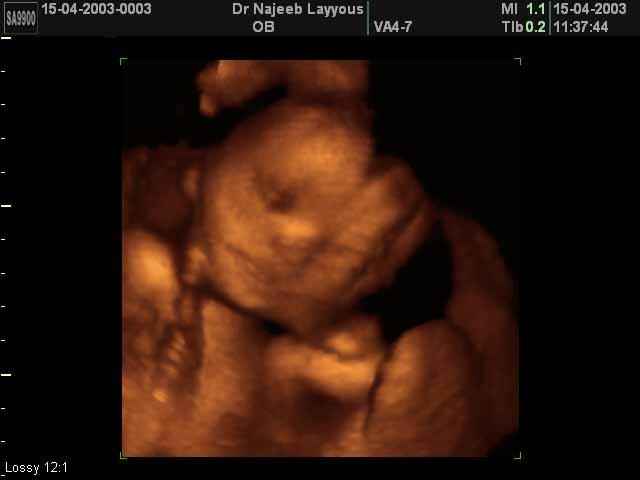

- تصرفات الجنين داخل الرحم

- صور لتصرفات الجنين داخل الرحم

صور لتصرفات الجنين داخل الرحم بجهاز الالتراساوند ثلاثي الأبعاد | الدكتور نجيب ليوس